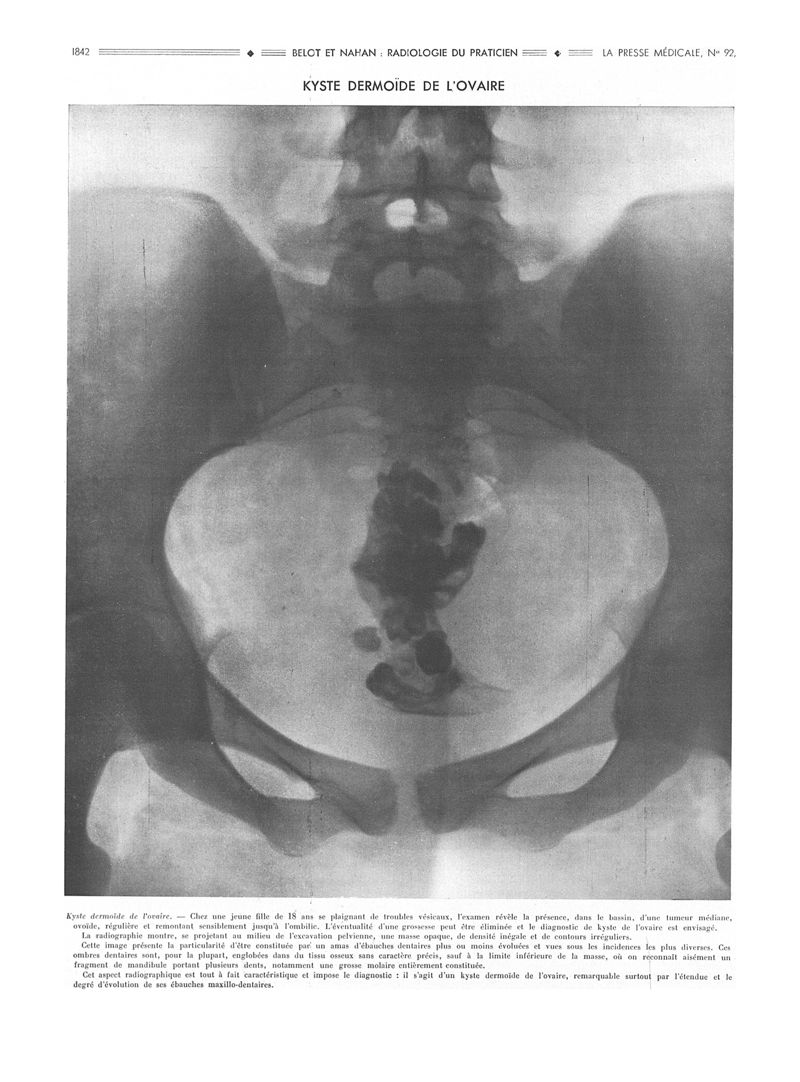

La Presse médicale - [Articles originaux]

1936, Articles originaux. - Masson et Cie, 1936.